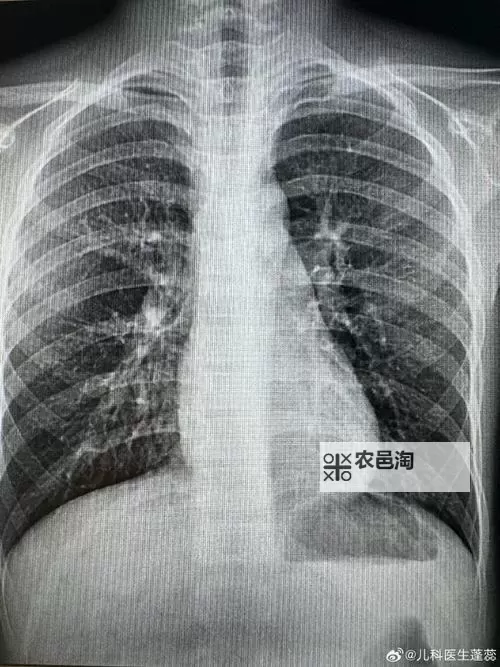

胸部影像检查,俗称胸片,是诊断肺部疾病、心脏异常及其他胸腔内疾病的重要手段。通过高质量的胸片,医生可以早期发现肺结核、肺炎、肺癌等严重疾病,及时采取措施,挽救生命。通常情况下,胸片检查需要一定的费用,但此次活动则打破了这一限制,面向广大市民免费开放,让更多人受益于现代医疗科技的便利。

此次活动的核心亮点在于“百分百曝光”,意味着每一位参与者都可以获得一份全面、清晰的胸部影像报告。专家团队利用先进的设备,确保每一张胸片的高质量和准确性,从而帮助筛查潜在的健康风险。更重要的是,通过专业医师的详细解读,公众可以了解自己的身体状况,增强健康意识,从而形成科学的生活习惯,为未来的健康保驾护航。